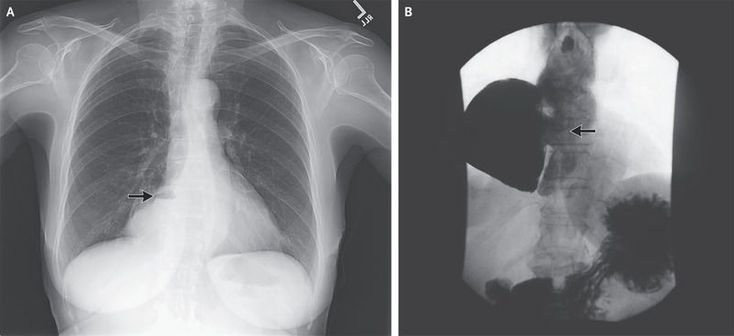

A 77-year-old woman with achalasia was evaluated in a gastroenterology clinic for intermittent dysphagia to solids, regurgitation of liquids and solids, and recurrent esophageal yeast infections over the previous 11 years, as well as a 7.7-kg (17-lb) weight loss over the previous 3 years. A chest radiograph showed a density containing an air–fluid level to the right of the heart (Panel A, arrow). Radiography of the esophagus revealed an epiphrenic diverticulum, 10 by 15 cm (Panel B, arrow), and delayed emptying at the gastroesophageal junction with esophageal dilatation and tortuosity, which are findings consistent with the patient's diagnosis of achalasia. Endoscopic examination confirmed the presence and position of the diverticular opening, and a yeast infection was confirmed by culture. Because of the patient's progressive symptoms, a laparoscopic resection of the diverticulum, Heller's myotomy, and Dor's fundoplication were performed, without complications. Epiphrenic diverticula typically arise just proximal to the lower esophageal sphincter. They are thought to be caused by ballooning of the esophageal mucosa and submucosa through a weakened area in the muscular layer as a result of increased intraluminal pressure, and they are commonly associated with an underlying motility disorder such as achalasia, as in this case. Two years after surgery, the patient remained free of symptoms.